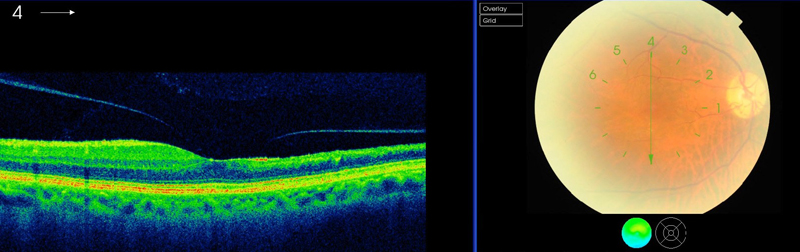

El pronóstico varía según el sitio de la oclusión arterial. La mayoría de los pacientes con ORAR recuperan la visión

1,50, mientras que la mejoría espontánea en la OACR es rara. En estudios experimentales la retina puede sobrevivir entre 90 y 100 minutos después de la oclusión mecánica de la ACR

51-53.

La AV en el momento de la presentación predice el resultado visual final en pacientes con OACR. En una serie de 34 casos consecutivos con OACR sólo el 35% de los ojos alcanzó una visión mejor de 0,2

54. En otra serie de 72 casos con OACR, solo en 4 ojos la AV fue superior a CD

55 (

Figura 6 y

Figura 7).

Figura 6. Esclerosis vascular secundaria a oclusión arterial antigua.

Figura 7. Tomografía de coherencia óptica: importante adelgazamiento retiniano en territorio de oclusión arterial.

Retinografía: muestra un émbolo cálcico a nivel papilar.